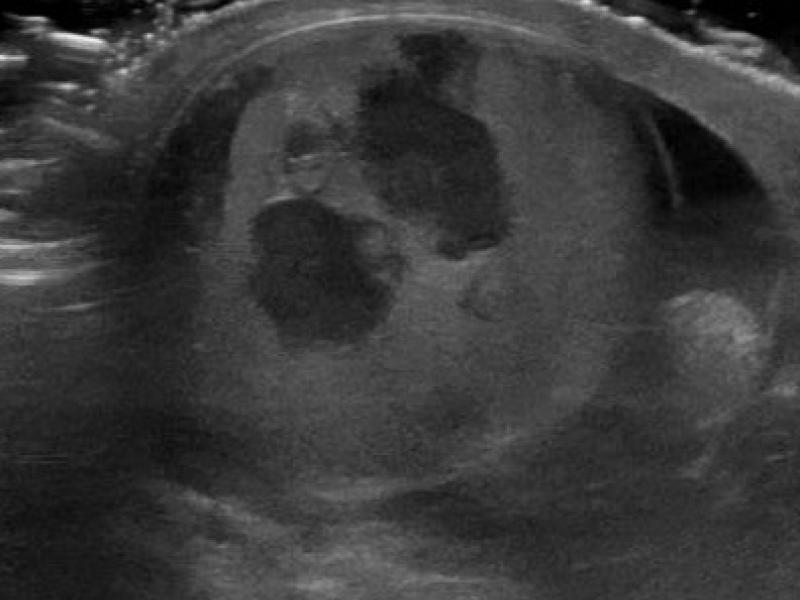

Left: Trans-abdominal curvilinear probe Right: Trans